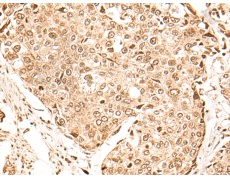

IHC positive control: |

Human thyroid cancer and human cervical cancer |